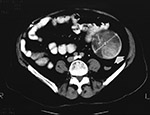

Gossypiboma is the term sometimes used to describe the foreign body reaction to a surgical sponge left within the body for a long period (figure: gossypiboma; figure gossypiboma on CT). The cotton matrix of the sponge forms the nidus of the foreign body reaction. Around the cotton nidus, there is surrounding fibrosis, retraction, and development of a foreign body granuloma (Sturdy, 1967; Kondo, 2018). The frequency of retained surgical foreign material is one per 1,000–1,500 laparotomies (Rappaport, 1990). Many patients are asymptomatic, and the retained sponge is discovered accidentally when the patient undergoes a radiologic study for some other reason.

Elderly man with a retained surgical sponge granuloma (gossypiboma) (arrow). Vertebroplasty cement has embolized to the patient's lungs. This was an incidental findings on a routine chest radiographic series. From Hunter, 2004a. Permission granted for use of images in this article by Radiological Society of North America (RSNA)